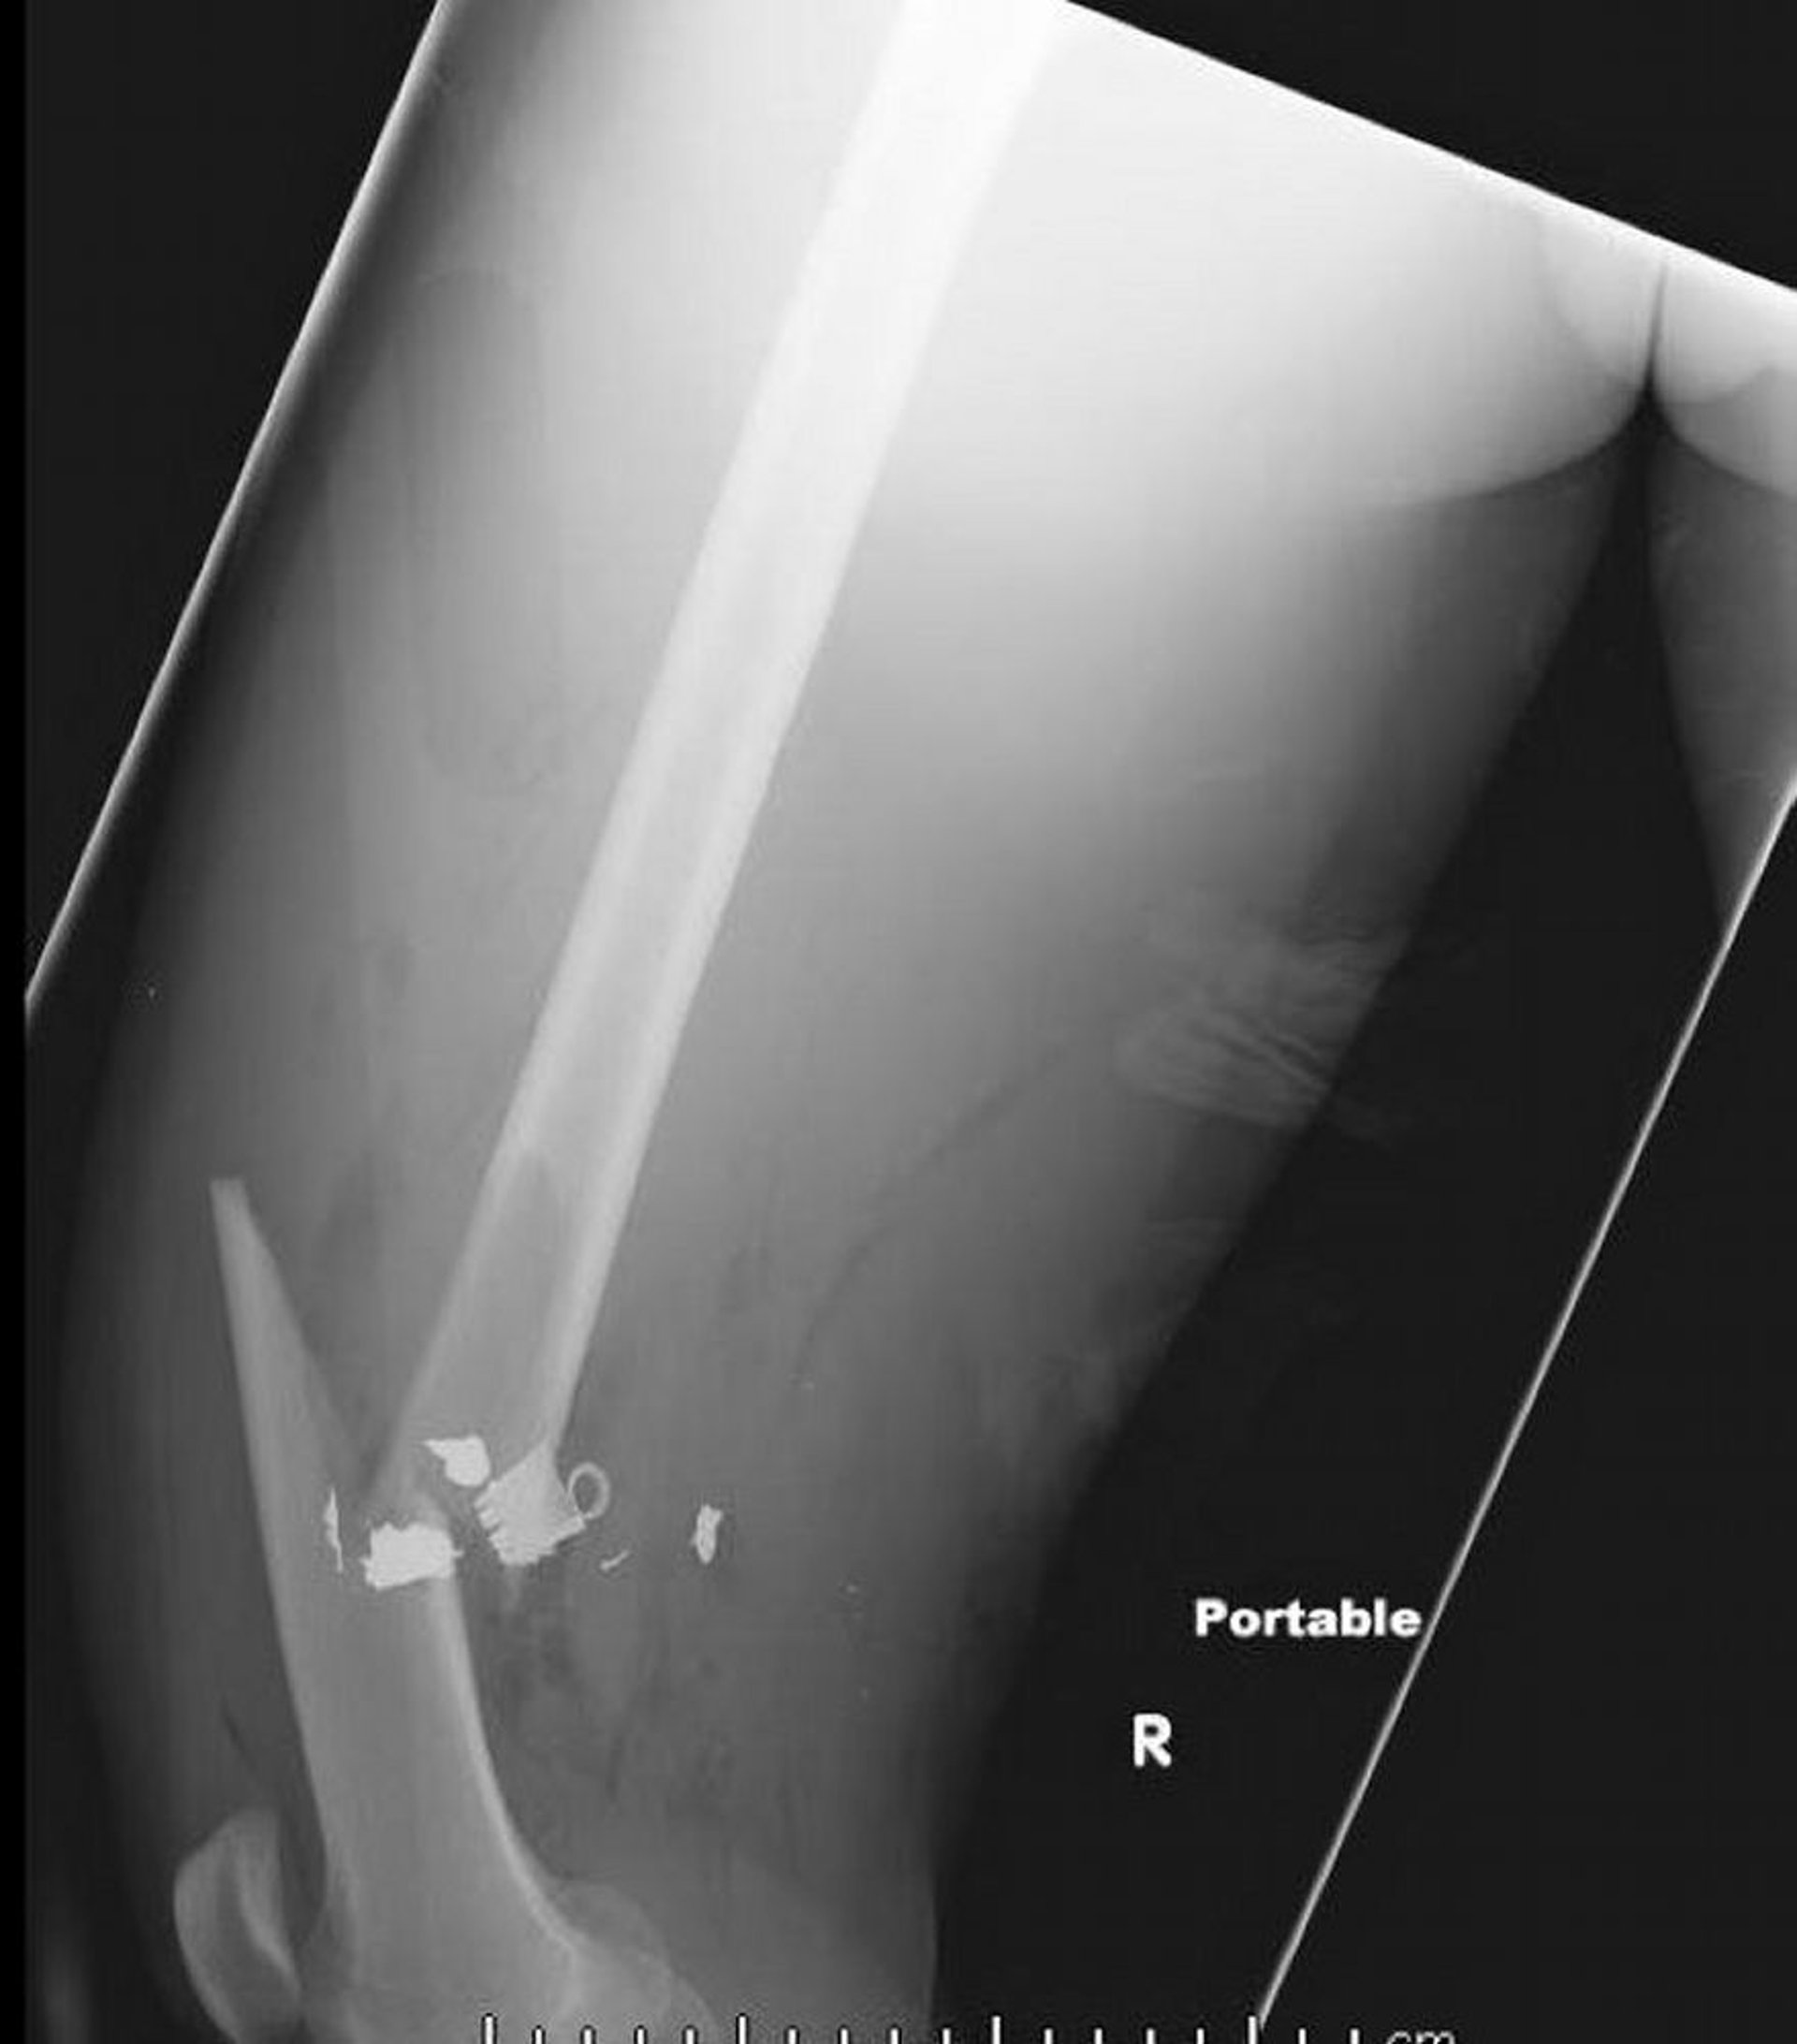

Femurfraktur in der Schaftmitte (2)

Diese Röntgenaufnahme des lateralen Oberschenkels zeigt eine Femurfraktur in der Schaftmitte mit Luft im Weichteilgewebe und zurückgebliebenen Fremdkörpern metallischer Dichte.

Image courtesy of Danielle Campagne, MD.